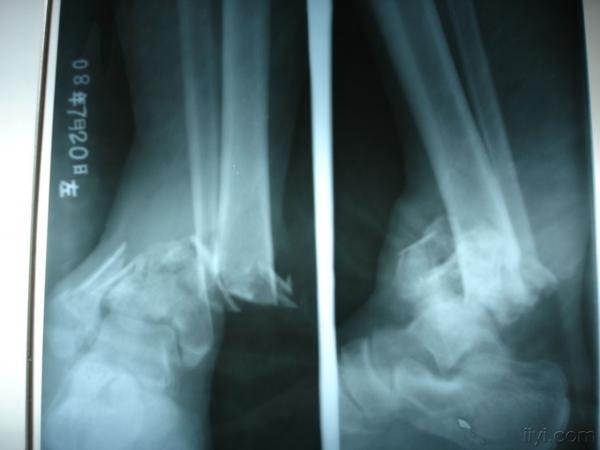

患者缘于半小时前在1.7米高处不慎跌下,左脚着地、折弯,立即出现剧痛、畸形、流血,由同事护送我科就诊。PE:神清、痛苦貌,生命体征平稳,心肺(-)、腹平软,CNS(-),左内踝处有一约3.5Cm的皮肤横裂口,胫骨远端骨折断端完全外漏,X光片如下

骨折特点:胫骨远端具有典型的不同程度的压缩粉碎性骨折,累及关节面关节软骨的原发性损伤以及永久性关节面不平整导致不良的预后。Pilon骨折约占下肢骨折的1%,胫骨骨折的3%--10%,约75%--85%的Pilon骨折并发有同侧腓骨骨折。随着建筑业和交通业的迅速发展,高能量损伤所致的胫骨Pilon骨折有增多的趋势。虽然治疗的手段不断修正和更新,但至今仍然是临床上一个棘手的问题,其并发症多、病残率高。)